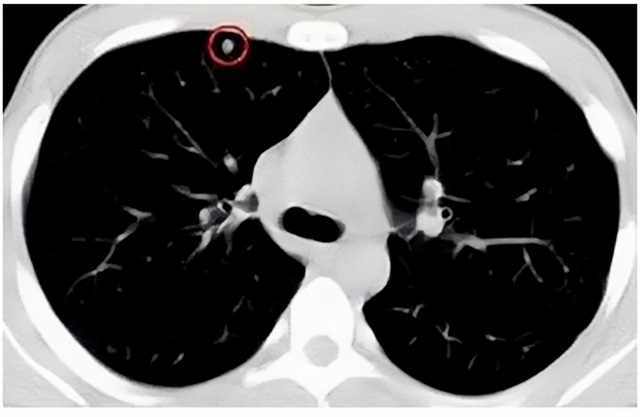

移動CT體檢車可以檢查肺結(jié)節(jié)發(fā)現(xiàn)早期肺癌

移動CT體檢車可以做肺部檢查。隨著多層螺旋CT肺部低劑量掃描的臨床應(yīng)用,目前很多人選擇肺部CT作為常規(guī)檢查項(xiàng)目,較大地提高了肺結(jié)節(jié)的檢出率。如果檢查發(fā)現(xiàn)肺部有肺結(jié)節(jié)是磨玻璃型的,小于5mm的微小結(jié)節(jié),大部分都是良性的。如果達(dá)到1CM以上的,很有可能有肺癌的機(jī)率。根據(jù)其內(nèi)密度不同可分為磨玻璃結(jié)節(jié)、實(shí)性結(jié)節(jié)、部分實(shí)性結(jié)節(jié)。根據(jù)其大小可分為肺大結(jié)節(jié)、小結(jié)節(jié)和微小結(jié)節(jié)。如果是炎癥性肺結(jié)節(jié),幾個(gè)月后復(fù)查有變化變小就不用做手術(shù)。如果CT再次復(fù)查結(jié)節(jié)沒有變化,沒有縮小就需要升級做病例檢查。病理檢查的確診性是最高的。是有沒患癌的標(biāo)準(zhǔn)。檢查發(fā)現(xiàn)早的話,規(guī)范手術(shù)治療,手術(shù)后5年的存活率很高的。肺癌這個(gè)要早發(fā)現(xiàn)早治療。

現(xiàn)在的移動CT體檢車的分辨率比X光高,CT掃描的圖像越來越薄顯像更清晰,檢查更準(zhǔn)確。得到了普及,肺結(jié)節(jié)的測出率很高的。但是顯浩告訴大家,肺結(jié)節(jié)不等于肺癌。雖然很多是良性,但是很多肺癌都是肺結(jié)節(jié)發(fā)展來的。 必須定期檢查復(fù)查。磨玻璃結(jié)節(jié),肺癌的機(jī)率較高。肺癌是惡性腫瘤病死率最高的。除了環(huán)境,遺傳,等因素。吸煙,從事煙霧工作行業(yè)的人員比較危險(xiǎn)。發(fā)病比例高。肺部疾病早發(fā)現(xiàn)早治療,依舊是肺部疾病的治療標(biāo)準(zhǔn)。

一旦CT檢查發(fā)現(xiàn)肺結(jié)節(jié),若不規(guī)律復(fù)查,檢查等同于白檢。所以在復(fù)查中,如果結(jié)節(jié)中發(fā)現(xiàn)有增大的趨勢,或大小發(fā)生了變化,我們必須提請注意及時(shí)治療,不要掉以輕心。移動CT體檢車的普及化,讓肺部檢查更準(zhǔn)確更高效。發(fā)現(xiàn)肺結(jié)節(jié)時(shí),及時(shí)就醫(yī)并進(jìn)行專業(yè)評估是確保準(zhǔn)確分類和采取適當(dāng)措施的關(guān)鍵。